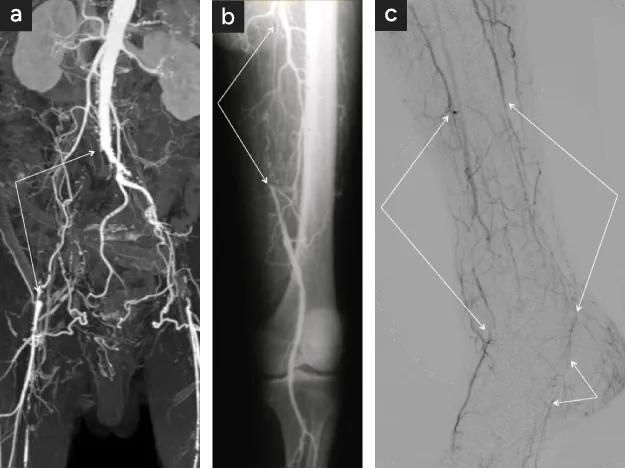

ASOでは3つの動脈閉塞の好発部位があります。

① 腸骨動脈(骨盤型閉塞)

② 大腿動脈(大腿型)

③ 下腿型(膝下動脈)〈図1〉

糖尿病の有無により病状は異なり、糖尿病がないASOは骨盤〜大腿型閉塞が多く、糖尿病のASOは下腿型が特徴です。

閉塞部位が異なると血行障害に対する治療(血行再建法)が異なってきます。いずれもバイパス手術が選択されますが、①では人工血管によるバイパスが第一選択〈図3〉、③では患者さん自身の下肢の静脈を用いるバイパスが第一選択です〈図4〉。

②では膝上までならば人工血管も使用できますが、静脈を用いるバイパスと比べ結果は良くありません。

①では人工血管以外にカテーテル治療の成績も良好ですので近年は人工血管バイパスよりも多く用いられます。

②に対するカテーテル治療成績は人工血管と同程度で良好とは言えませんが、短い狭窄病変ならば選択して良い方法です。

図1

図1. 下肢ASO病変の好発部位

• 大動脈~腸骨動脈(骨盤型)

• 浅大腿動脈(大腿型)

• 脛骨・腓骨動脈(下腿型)